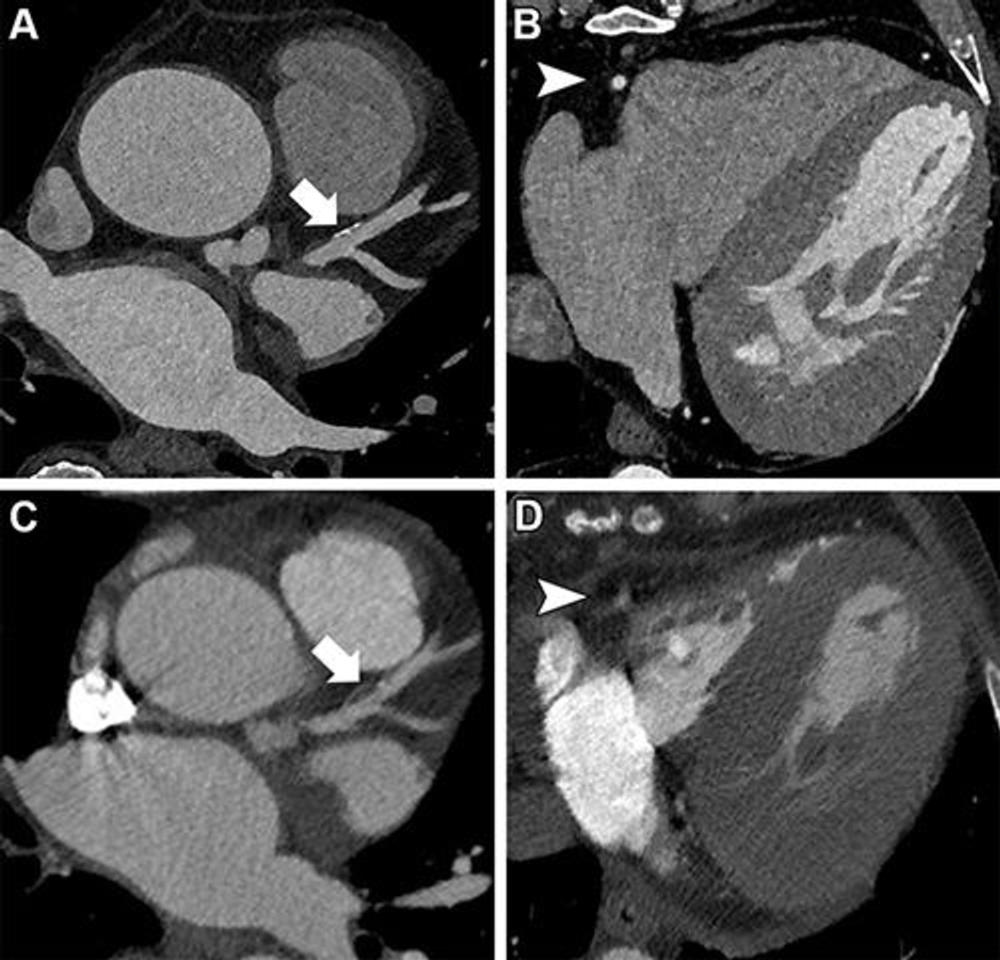

Figure 3. Images in a 67-year-old man with severe aortic valve stenosis recurrence after surgical aortic valve replacement 6 years ago and referral for valve-in-valve transcatheter aortic valve replacement CT. (A, B) Ultrahigh-resolution (UHR) coronary CT angiography (CCTA) on a first-generation dual-energy photon-counting scanner. (C, D) Cardiac CT images obtained with a second-generation dual-source energy-integrated CT scanner for planning this participant’s first aortic valve replacement 6 years prior to UHR CCTA. Note the superior image quality of UHR CCTA regarding vessel sharpness of the right coronary artery (arrowhead in B and D) and plaque visualization in the left anterior descending artery (arrow in A and C). Heart rates were comparable between UHR CCTA and cardiac CT (59 beats per minute vs 64 beats per minute, respectively), and contrast media and scan mode (electrocardiography-synchronized retrospective spiral scan) were similar.